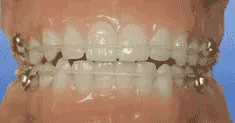

As a practicing general dentist, I see many adults whose chief complaint is crowding of the lower teeth — sometimes upper as well. Many received orthodontic care when they were younger and have not worn their retainers since then. Others never had any orthodontic treatment, yet complain that their lower teeth are suddenly becoming crowded.